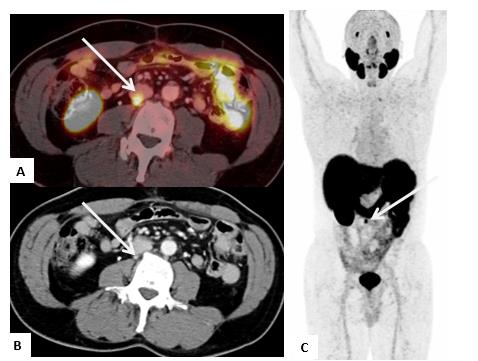

El PET/CT-PSMA también es sensible en la detección de metástasis viscerales, las cuales son menos frecuentes (Figura 7).